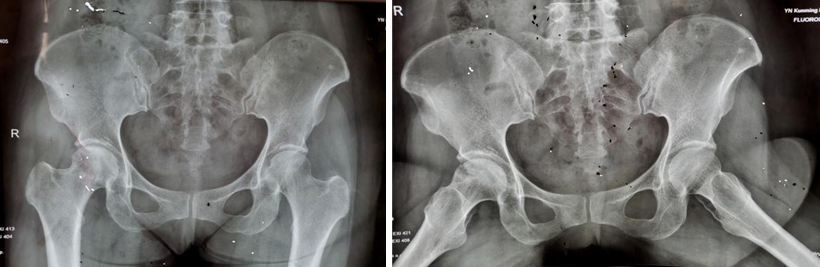

两年多前,34岁的王先生因双髋部疼痛伴活动受限4月余,在家人的搀扶下,一脸痛苦地来到av线上 骨科就诊。杨振东副主任医师接诊了这位患者,该患者饮酒史10年,每日2两,戒酒1月,右髋外旋活动受限,左髋活动正常,右髋“4”字试验阳性,结合影像学资料显示,该患者右侧股骨头凹凸不平、黯淡无光,且有部分塌陷,诊断为右侧股骨头坏死。

术后12个月和24个月,患者来院复查,影像片子显示患者右侧股骨头髋臼平整光滑,股骨头圆润光滑,股骨头内骨小梁密度均匀,已恢复至正常股骨头状态,几乎与正常人股骨头无异。患者随访时说:“来医院之前,我独立行走都困难,短短几米的距离,我可能要花费三四分钟才能走完。手术之后,我不仅可以健步如飞,还能做下蹲等动作,也不必担心重体力劳动导致股骨头无法承受的问题,这个手术真的是太好了,不仅救了我,也救了我一家人……”